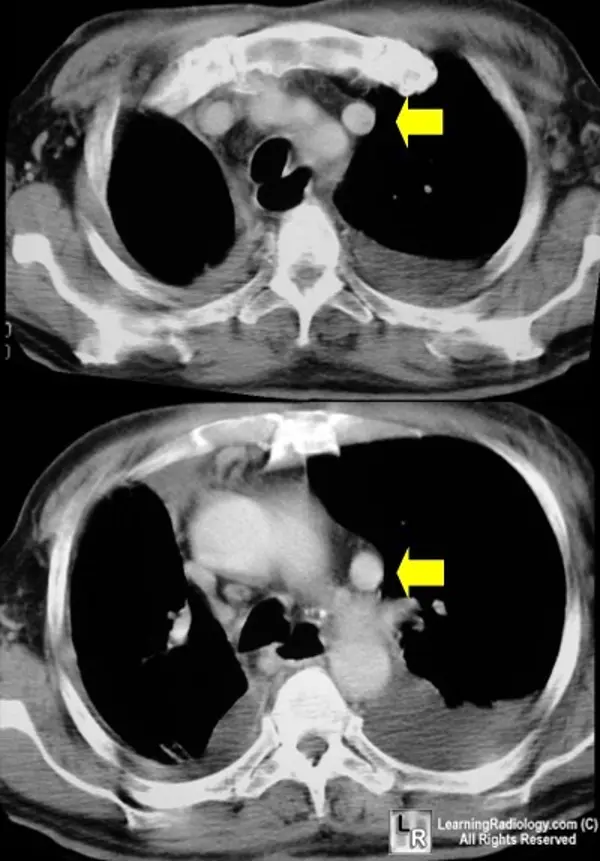

• Persistent Left-sided SVC “is the most common congenital venous anomaly in the chest, and in a minority of cases can result in a right-to-left shunt.” (Source)

• Most cases are asymptomatic and are noted incidentally on CT chest